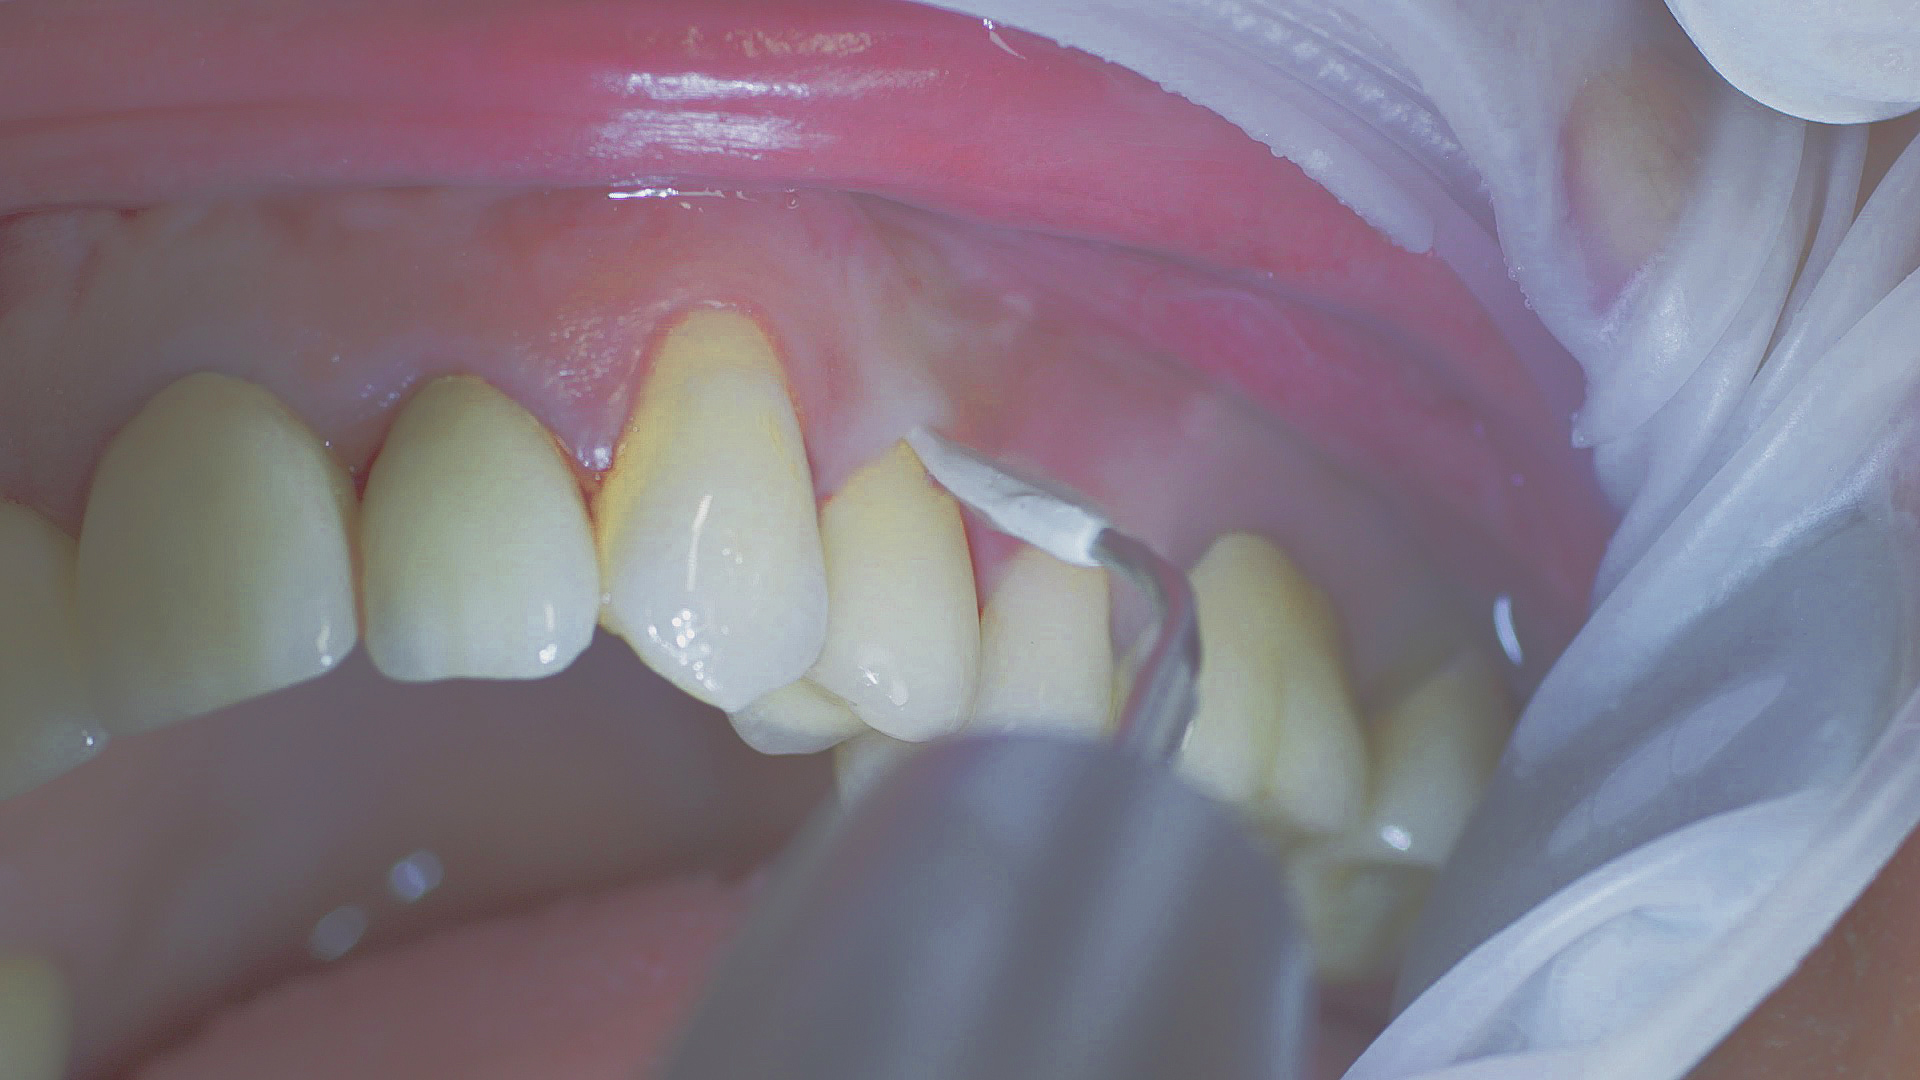

In the periodontal aftercare subsequent to implantation, soft (biofilm) and hard coatings are regularly professionally and mechanically removed.[16, 17] In the subgingival and supragingival areas, ultrasonic devices are generally used for this (Fig. 4), in combination with manual instruments where necessary. Alternatively, subgingival air polishing can be used in combination with periodontal attachments and powders.[18]